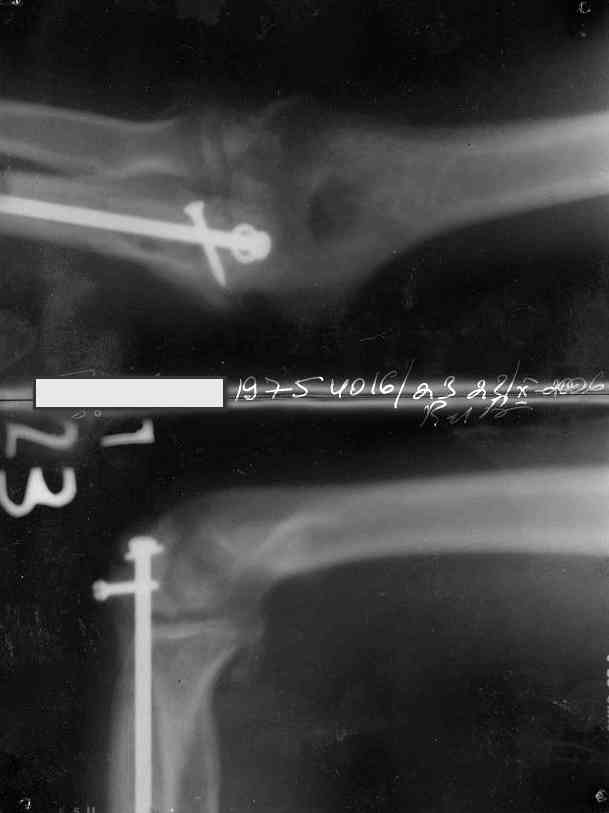

У меня 23 июня 2006 года был перелом отростка лучевой кости с вывихом правой руки. Через неделю мне сделали операцию. В гипсе проходил 1.5 месяца. Когда сняли гипс, выяснилось что отросток не сросся (щель 4-5 мм). Через 3 недели мне сделали операцию в другой клинике. Сняли гипс через 4 недели. Все вроде хорошо. Отросток прирос. Началась разработка руки.

• Кликните для загрузки файла 1.jpg

13KB (14161 bytes)

Снимки от 22.10. Желательно прислать свежие снимки, можно и фото свища.